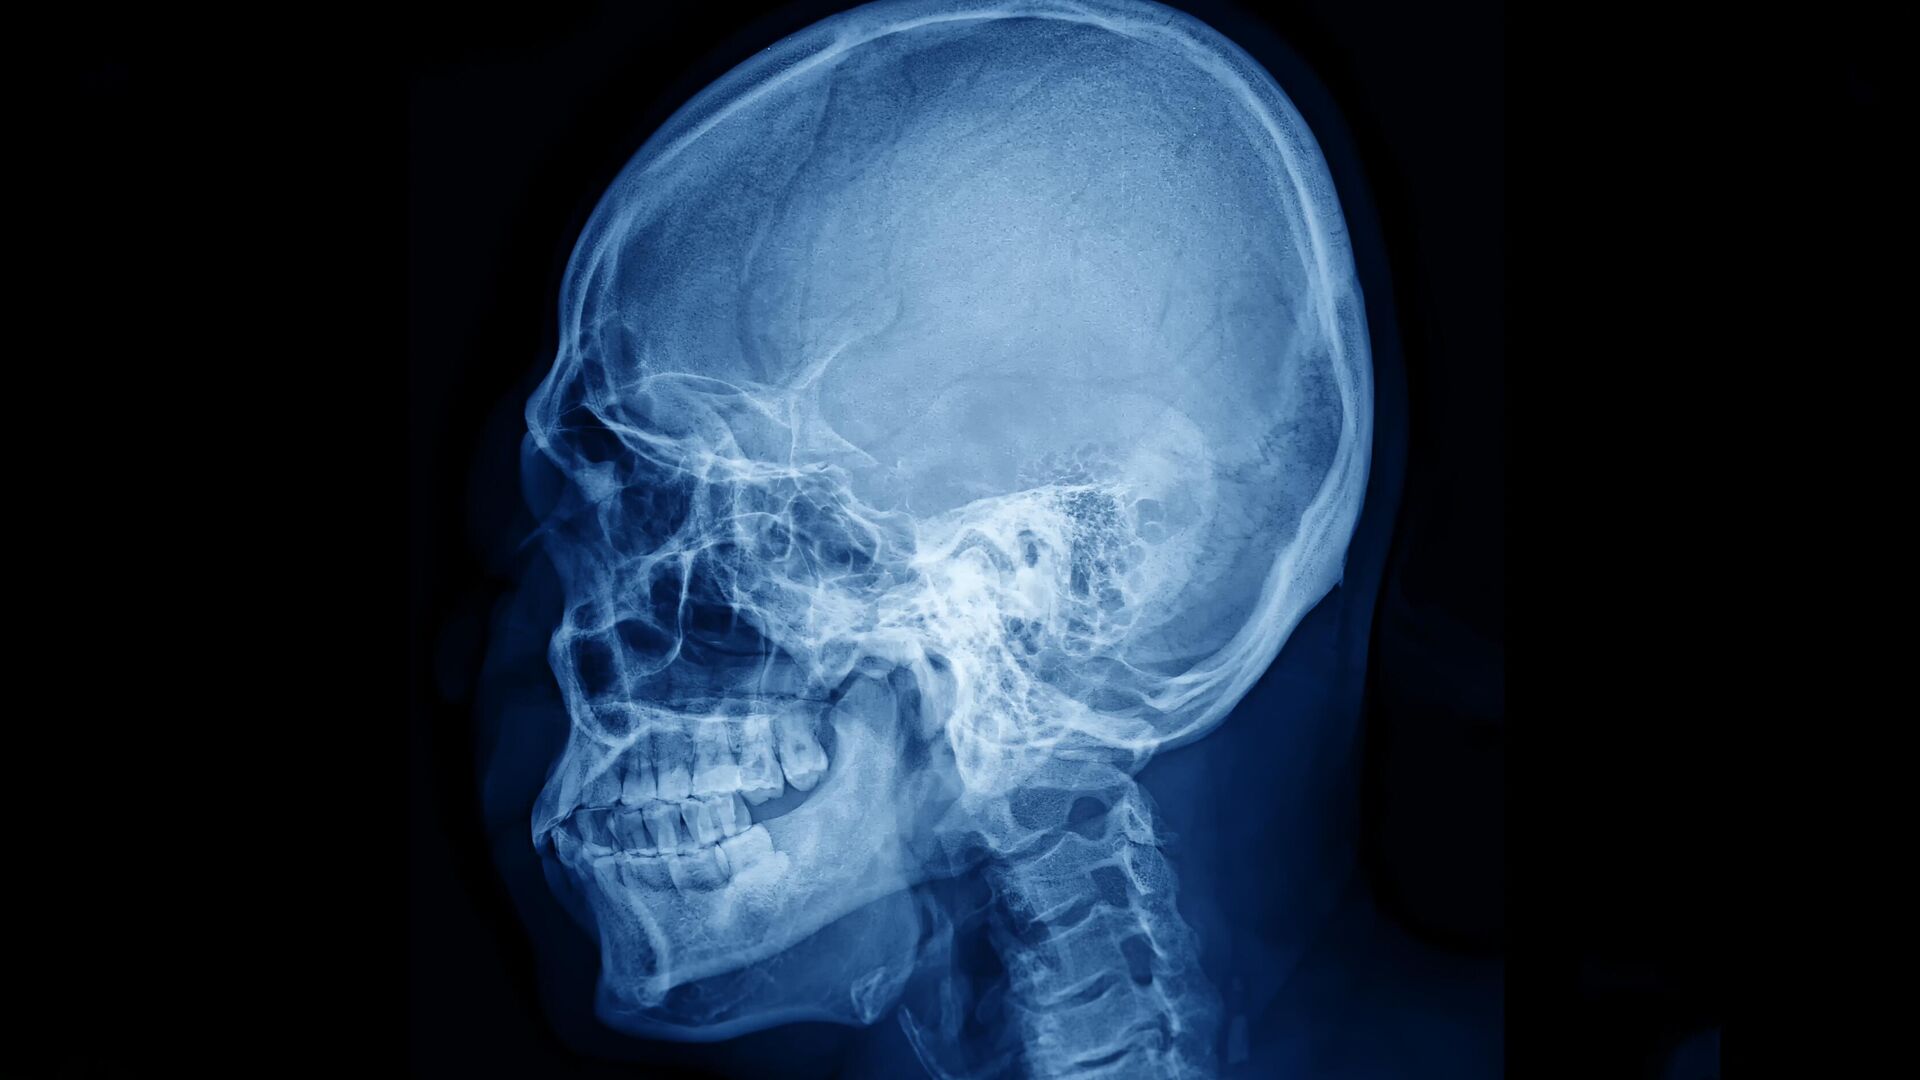

Современные методы визуализации сосудов головного мозга сталкиваются с серьезными техническими ограничениями, связанными с особенностями костной ткани черепа. Для получения четких изображений сосудистой сети часто требуется либо значительное истончение костей, либо создание отверстий в черепной коробке, что является инвазивной процедурой и связано с определенными рисками для пациента. Основная сложность заключается в том, что костный материал сильно рассеивает лазерный свет, используемый в ряде передовых диагностических методик, что приводит к размытию и искажению получаемых изображений.

Одним из таких методов является лазерная спекл-контрастная визуализация, которая широко применяется для наблюдения за кровотоком в головном мозге. Как пояснил младший научный сотрудник лаборатории биомедицинской фотоакустики СГУ Юрий Сурков, лазерный свет, проходя через костные структуры, испытывает сильное рассеяние, что существенно снижает качество карт сосудов и перфузии мозга. Это ограничивает точность диагностики и усложняет оценку состояния мозгового кровообращения.

Современные методы визуализации мозгового кровотока играют ключевую роль в диагностике и исследовании сосудистых заболеваний, однако качество получаемых изображений часто ограничено из-за низкой контрастности сосудов на фоне костной ткани черепа. В ответ на эту проблему группа ученых из Самарского государственного университета (СГУ) совместно с коллегами из Сеченовского университета, Национального медицинского исследовательского центра нейрохирургии имени Н. Н. Бурденко, Национального исследовательского университета «МИЭТ» и Университета Астон в Бирмингеме (Великобритания) разработала инновационный метод, позволяющий приблизительно в два раза повысить контрастность сосудистых изображений, получаемых при наблюдении мозгового кровотока через целый череп.

Ранее при визуализации сосудов через череп многие мелкие сосуды и тонкие ветви сосудистой сети оставались незаметными, поскольку их контрастность была недостаточной на фоне плотной костной ткани. Благодаря новому подходу, сосуды становятся значительно более четкими и различимыми, что позволяет выявлять ранее скрытые участки сосудистой сети и получать более детальную картину кровотока. Это сравнимо с ситуацией, когда вы смотрите на пейзаж через матовое стекло: раньше изображение было размытым и нечетким, а теперь оно становится прозрачным и ярким, позволяя рассмотреть мельчайшие детали.

Первый метод заключается в том, чтобы временно повысить прозрачность черепа, подобно тому, как матовое стекло становится более прозрачным при определенных условиях. В нашем случае мы предлагаем использовать желтый пищевой краситель тартразин (Е102), который широко применяется в пищевой промышленности — в напитках, пюре, йогуртах и консервированных фруктах — для увеличения прозрачности костной ткани черепа. Это позволяет свету проникать глубже и улучшает визуализацию кровотока.